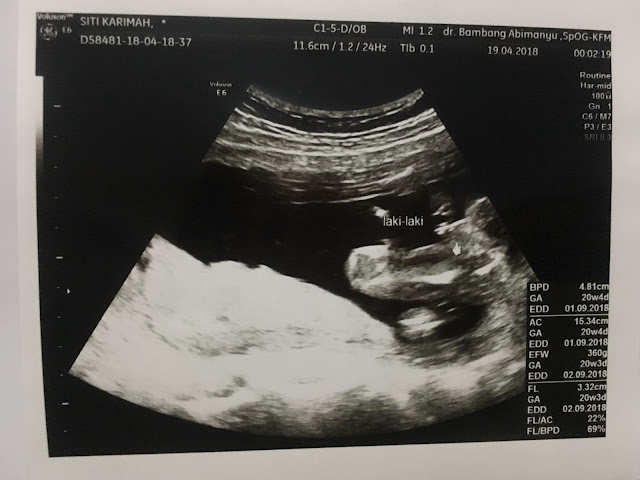

Laki-laki lagi nih hasilnya hihi, alhamdulillah sehat. Kebetulan mau memasuki bulan puasa pas kontrol ini, jadi sekalian tanya-tanya aman nggak kalo puasa, alhamdulillah dr Bambang pro puasa jadi aku semakin PD buat puasa.

Next kontrol, sebenernya belum sebulan sih tapi berhubung mau mudik ke Jakarta, aku perlu surat rekomendasi naik pesawat terbang. Jackpot! Ketemu dokter nggak beres banget gara-gara dokter Bambang udah full booked sedangkan aku butuh surat rekomendasi terbang as soon as possible. Ini hasil USG di dokter nggak beres itu: